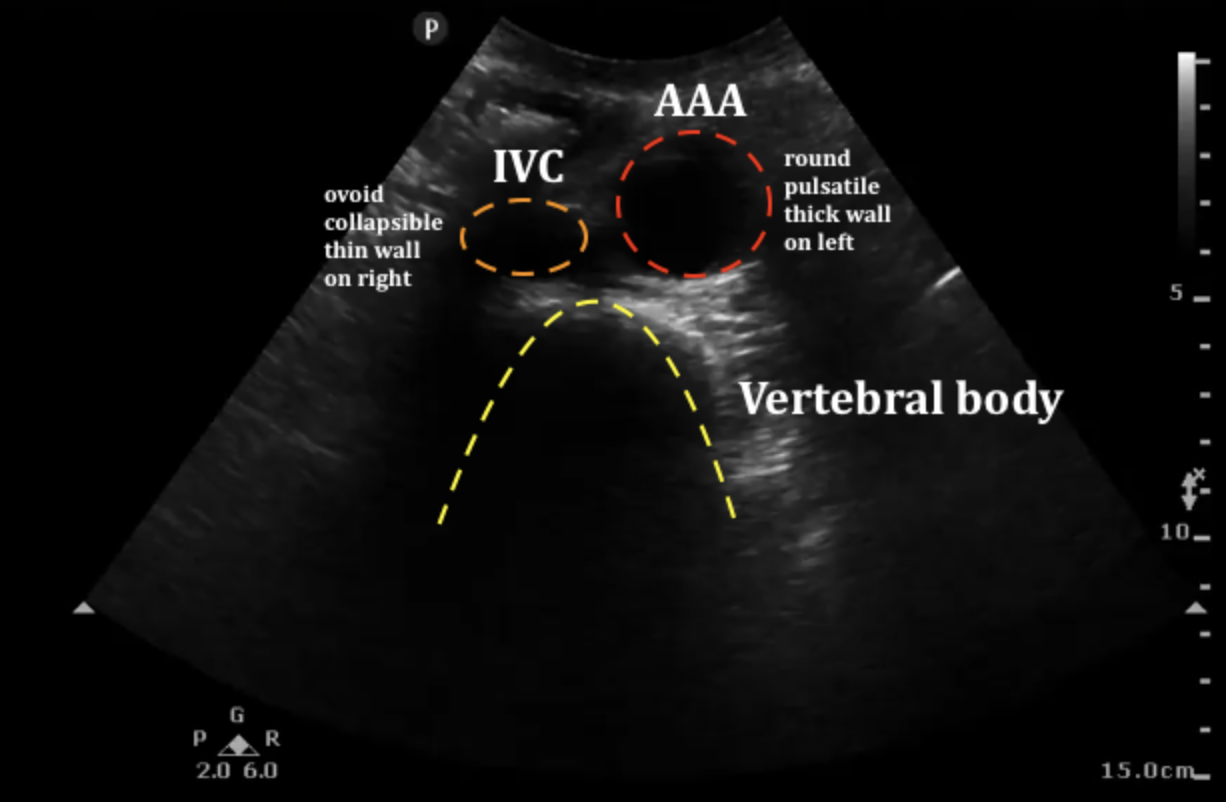

복부 대동맥류(AAA)

- 직경 3 cm 이상, 또는 정상 대비 50% 이상 확장된 상태를 말합니다.

- 5.5 cm 이상이면 파열 위험이 급격히 증가하므로 수술·스텐트 삽입을 검토합니다.

- 남성·흡연·고혈압·고지혈증·가족력이 주요 위험인자입니다.